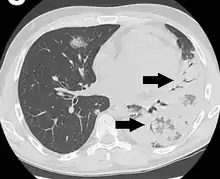

An air bronchogram is defined as a pattern of air-filled bronchi on a background of airless lung.[1]

In pulmonary consolidations and infiltrates, air bronchograms are most commonly caused by pneumonia or pulmonary edema (especially with alveolar edema).[2][3]

Lung nodules

For lung nodules, air bronchograms used to be associated with infectious causes of consolidation and, therefore to be benign. However, in the setting of a lung nodule, an air bronchogram is actually more frequent in malignant than in benign nodules.[1][4] studied the tumour-bronchus relationship and described five types:[1]